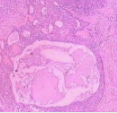

皮肤屏障的损伤或功能障碍往往与许多皮肤病的发生发展密切相关。在皮肤病的防治过程中,对皮肤屏障的保护和修复已成为一个重要环节。胶原贴敷料由于成分简单、安全性高、生物相容性好等优点,在皮肤屏障修复中发挥着重要作用。胶原贴敷料的核心成分为胶原蛋白,胶原蛋白在促进皮肤抗炎、修复、抗衰老方面具有其独特的优势。胶原贴敷料在临床应用已20 余年,前期通过大量的基础与临床研究验证了其临床疗效与安全性。为更好地指导临床医师规范、合理使用胶原贴敷料,就胶原贴敷料在皮肤屏障修复及创面愈合中的临床应用形成专家共识。